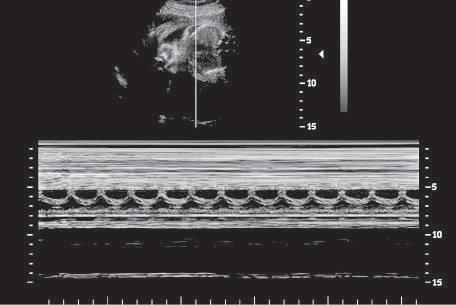

Another simple form of imaging, M-mode (motion-mode) ultrasound, displays echo amplitude and shows the position of

changes of echo amplitude and position with time. Display of changes in echo position is useful in the evaluation of rapidly moving structures such as cardiac valves and chamber walls. Here, the three major moving structures in the upper gray-scale image of the fetus are recorded in the corresponding M-mode image and include the near ventricular wall (A), the interventricular septum (B), and the far ventricular wall (C). The baseline is a time scale that permits the calculation of heart rate from the M-mode data.

moving reflectors (Fig. 1.12). M-mode imaging uses the brightness of the display to indicate the intensity of the reflected signal. The time base of the display can be adjusted to allow for varying degrees of temporal resolution, as dictated by clinical application. M-mode ultrasound is interpreted by assessing motion patterns of specific reflectors and determining anatomic relationships from characteristic patterns of motion. Currently, the major application of M-mode display is evaluation of embryonic and fetal heart rates, as well as in echocardiography, the rapid motion of cardiac valves and of cardiac chamber and vessel walls. M-mode imaging may play a future role in measurement of subtle changes in vessel wall elasticity accompanying atherogenesis.

FIG. 1.12 M-Mode Display. M-mode ultrasound displays